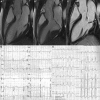

Methods and results: Thirty-six (27 female patients; median age: 44 years) arrhythmic MVP patients with LV late gadolinium enhancement on cardiac magnetic resonance and no or trivial mitral regurgitation, and 16 (6 female patients; median age: 40 years) MVP patients without LV late gadolinium enhancement were investigated by morphofunctional cardiac magnetic resonance. Mitral annulus disjunction (median: 4.8 versus 1.8 mm; P<0.001), end-systolic mitral annular diameters (median: 41.2 versus 31.5; P=0.004) and end-diastolic mitral annular diameters (median: 35.5 versus 31.5; P=0.042), prevalence of posterior systolic curling (34 [94%] versus 3 [19%]; P<0.001), and basal to mid LV wall thickness ratio >1.5 (22 [61%] versus 4 [25%]; P=0.016) were higher in MVP patients with late gadolinium enhancement than in those without. A linear correlation was found between mitral annulus disjunction and curling (R=0.85). A higher prevalence of auscultatory midsystolic click (26 [72%] versus 6 [38%]; P=0.018) was also noted. Histology of the mitral annulus showed a longer mitral annulus disjunction in 50 sudden death patients with MVP and LV fibrosis than in 20 patients without MVP (median: 3 versus 1.5 mm; P<0.001).

Conclusions: Mitral annulus disjunction is a constant feature of arrhythmic MVP with LV fibrosis. The excessive mobility of the leaflets caused by posterior systolic curling accounts for a mechanical stretch of the inferobasal wall and papillary muscles, eventually leading to myocardial hypertrophy and scarring. These mitral annulus abnormalities, together with auscultatory midsystolic click, may identify MVP patients who would need arrhythmic risk stratification.